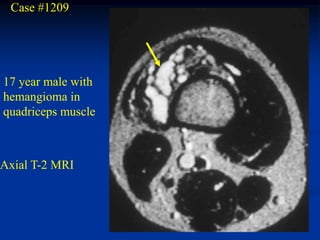

Case #1209

17 year male with

hemangioma in

quadriceps muscle

Axial T-2 MRI

Case #1209 17 yearmale with hemangioma in quadriceps muscle Axial T-2 MRI